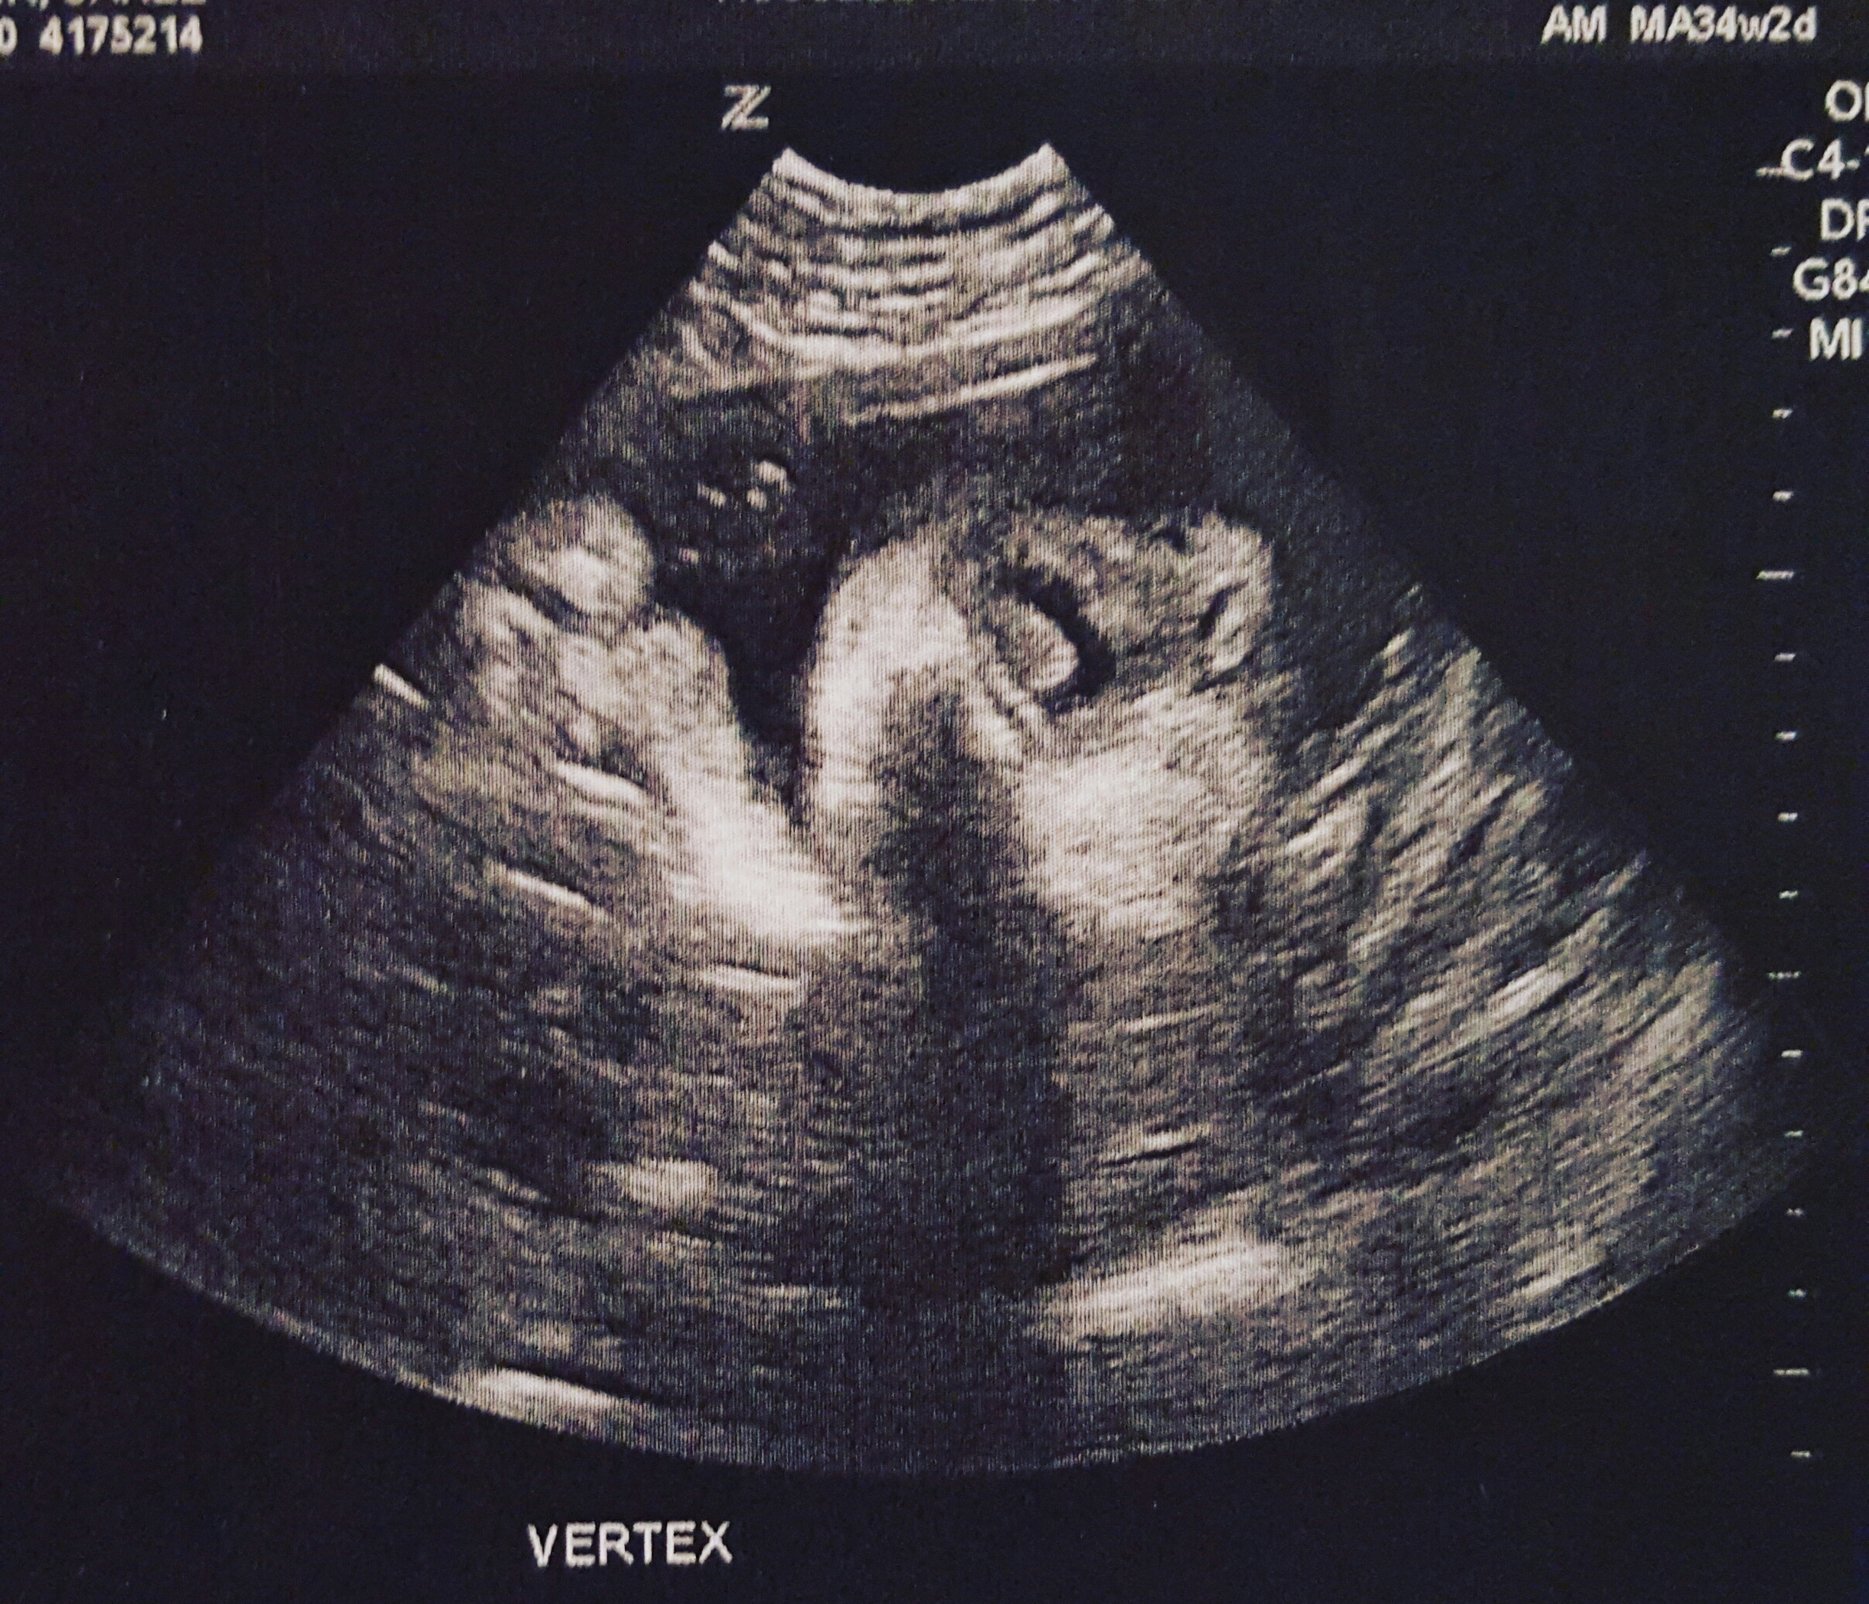

Baby H at my 18w U/S yesterday... After over an hour of looking and measuring and not being able to see the sex due to LO keeping the legs crossed, I was told to empty my bladder and we would try again. LO not only uncrossed it's legs, but completely flipped over... It's a Girl!